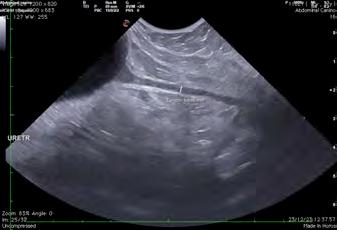

En los tejidos blandos junto al aspecto caudodistal del fémur, se visualizó una estructura redondeada, de 3 cm de diámetro y de atenuación líquido/tejido blando en precontraste, con un realce marcado postcontraste sugestivo de estructura vascular (Figs. 2 y 3). La vena y arteria femoral derecha presentaban apariencia normal hasta el aspecto distal del fémur, donde la vena femoral parecía conectar con la estructura descrita. La arteria femoral quedaba en íntimo contacto con dicha estructura, aunque no parecía estar conectada. Este hallazgo era compatible con una dilatación aneurismática afectando a la vena femoral. Distalmente a esta lesión, la arteria y vena poplíteas se observaban ligeramente más distendidas en comparación al lado contralateral. También había un leve aumento de atenuación de la grasa subcutánea de forma difusa distal a la lesión compatible con edema subcutáneo.

Figura 2. (A) Imagen de TC en ventana tejidos blandos, tras la administración de contraste, reconstruida en plano sagital y MIP (proyección de máxima intensidad). Se observa una estructura redondeada con marcada captación de contraste caudal al fémur y caudodistal al defecto femoral. (B) Imagen de TC en ventana de tejidos blandos, tras la administración de contraste, reconstruida en plano sagital oblicuo y MIP. Detalle de la lesión descrita en (A) y de su relación con la vascularización regional.

Figura

A B

Figura 3. (A) Imagen de TC reconstruida en Volumen Rendering (3D), tras administración de contraste (visión caudal). Se observa, caudalmente al aspecto distal de la diáfisis femoral, una estructura redondeada con gran captación de contraste (flechas naranjas) aparentemente conectada con la vena femoral y en íntima relación con la arteria femoral. (B) Imagen de TC reconstruida en Volumen Rendering (3D), tras administración de contraste (visión medial oblicua), donde se observa la estructura vascular descrita en (A) (flecha naranja).